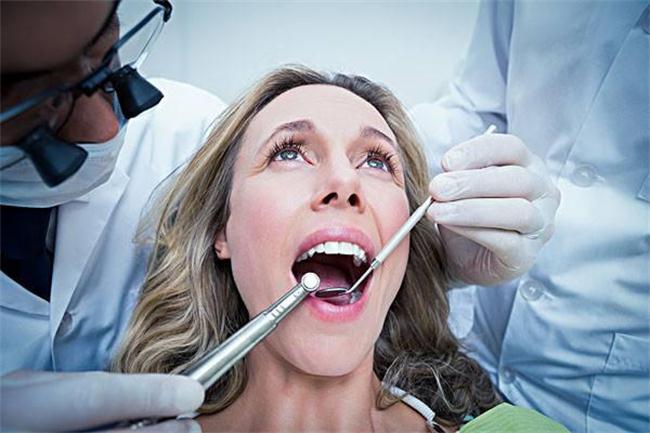

健康侦查员:牙医

jpeg,454x438,27688b